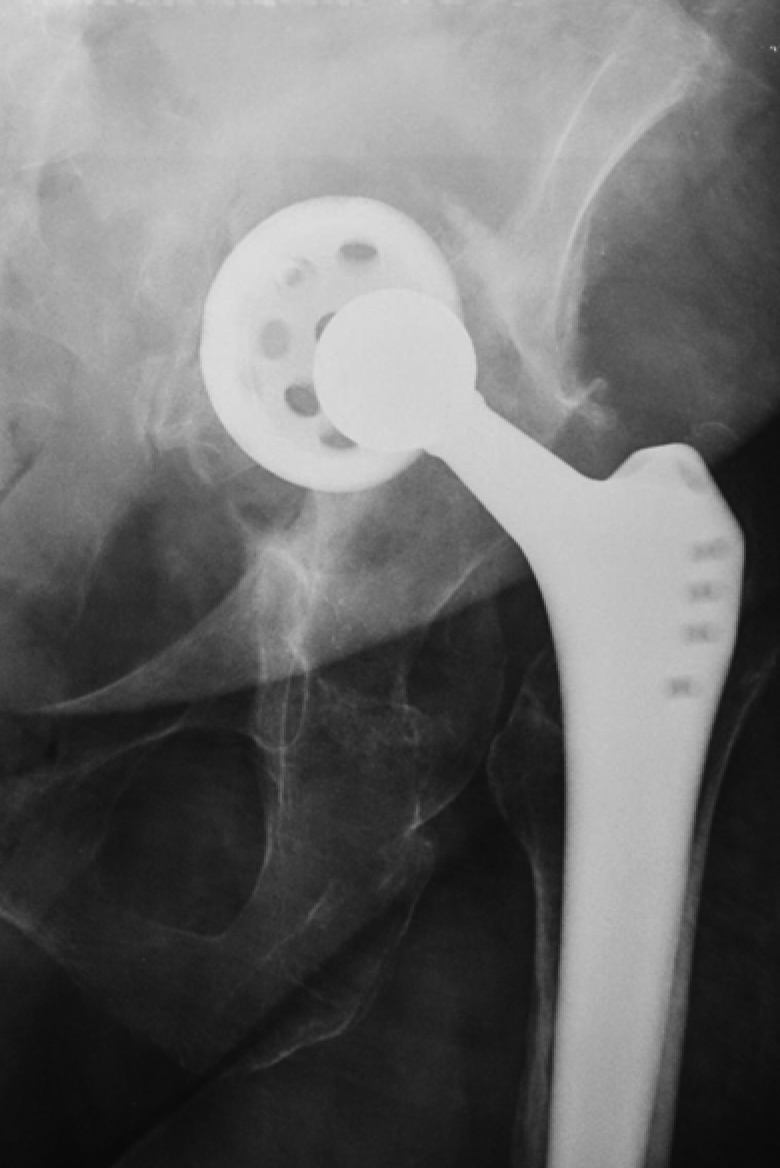

Lytic defects and complete defects of the anterior column, despite their extent, require the restoration of the sphericity of the acetabular region, which can be reconstructed using bone grafts, augments, and standard hemispherical components (Figure 2 a, b).

Figure 2. Various options for acetabular reconstruction in Paprosky type 3B defect: a — lytic acetabular defect reconstructed using impaction bone grafting with implantation of a standard cemented acetabular component; b — complete anterior column defect reconstructed with an augment and a hemispherical acetabular component; c — complete medial wall defect reconstructed with augmentation and combined implantation of a hemicap cage; d — combination of complete medial wall and anterior column defects reconstructed with a Burch-Schneider antiprotrusio cage and a cemented acetabular component; e — combination of complete medial wall and posterior column defects reconstructed with a patient-specific acetabular component

Reconstruction of complete medial wall defects, as well as combined complete defects of the medial wall and anterior column, requires the use of antiprotrusio devices to ensure the stability of the acetabular component. For this combination of defects, a wide range of types and sizes of standard cages may be necessary (Figure 2 c, d). In cases of combined complete defects of the medial wall and posterior column — the most challenging in terms of biomechanical stability of the acetabular component — there is a need for a highly reliable primary fixation of the implant, which cannot always be achieved with standard revision systems (Figure 2 e).